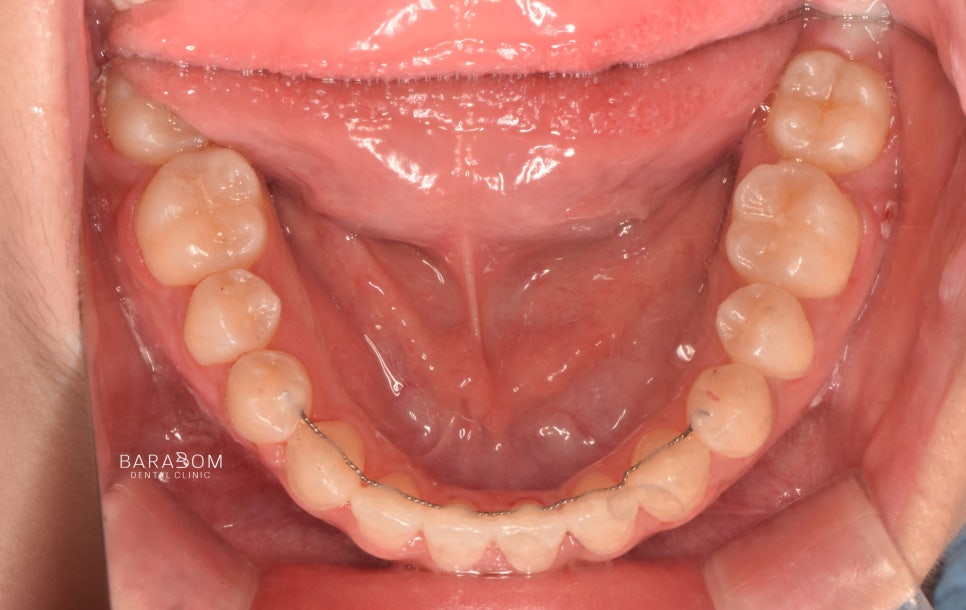

안모의 문제뿐만 아니라

부정교합도 함께 관찰됩니다.

안모와 동일하게 좌우

다른 문제를 가지고 있죠.

1️⃣좌측은 일부 치아가

거꾸로 물리는 반대교합 양상이

확인됩니다.

이런 경우 불안정한 힘이

치아에 가해져 파절로

이어질 수 있습니다.

2️⃣우측은 앞니의 끝부분 즉 절단연끼리

맞물리고 있는데요,

이를 절단 교합이라 부릅니다.

이렇게 맞물리는 양상 역시

힘을 고르게 분산시키기 어려워

절단연 파절로 이어질 수 있으며

턱관절에 안정을 찾기 어렵고

과도한 긴장 상태를 유지하게 됩니다.

윗니가 아랫니를 덮는 것이

정상적인데, 이 경우

정반대로 아래가 위를 덮는 듯한

모습이 관찰됩니다.

✅더불어 구치부의 맞물림 역시

올바르지 못한데요,

윗턱 성장 부전이 있어

골격성 3급으로 진단됩니다.

더불어 아랫턱이 좌측으로 변위되며

비대칭을 이루고 있습니다.

치료를 받은 지 17개월 가량이 지난 후 모습입니다.

1️⃣반대 및 절단 교합 양상이

모두 해소되었으며,

2️⃣골격적인 문제의 한계를 넘어

아랫턱과 윗턱이 조화를

이루는 모습이 관찰됩니다.

또한 윗니가 아랫니를 덮으며

정상적인 피개량을 가지고 있는데요,

하악 전체 치열 후방 이동과

상악 앞니의 정출을 통해

교합의 안정과 함께

심미를 되찾은 모습입니다.